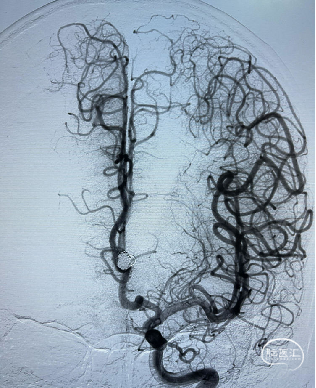

术后影像

术后多角度造影显示动脉瘤致密填塞,其他血管显影正常。术后CT无异常,mRS 0 分。

术后CT未见异常,mRS 0 分,无神经系统症状和体征,计划术后半年后复查DSA